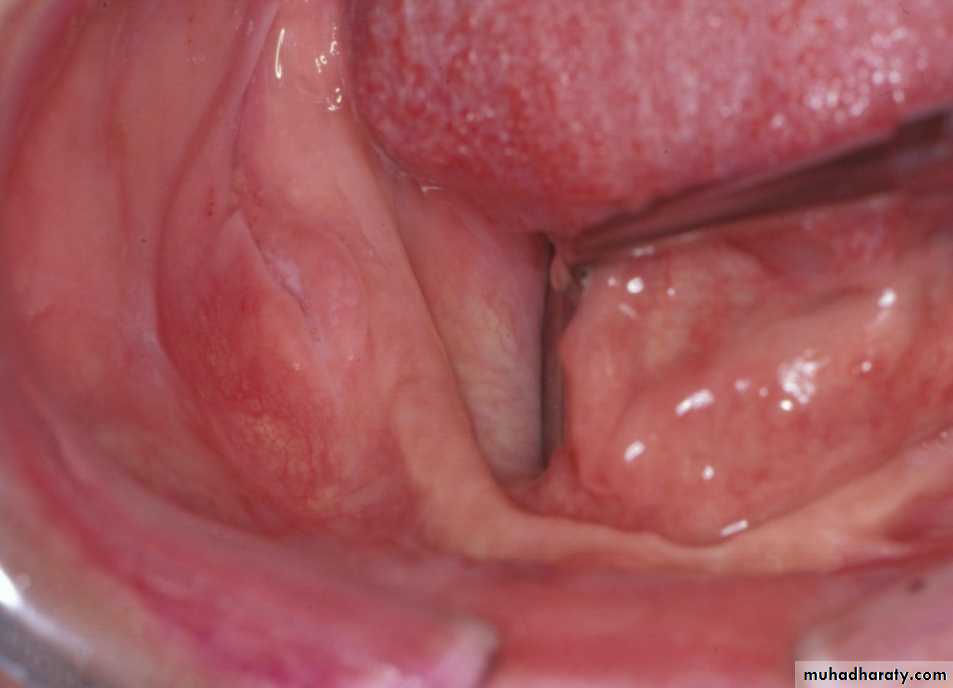

Preprosthetic Surgeryc. Gingivoplasty or frenectomy for flabby ridge tissue or high frena that interfere with support or retention

Gingivoplasty

Preprosthetic Surgery

c. Frenectomy1

2

4

3